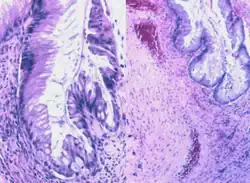

Histology